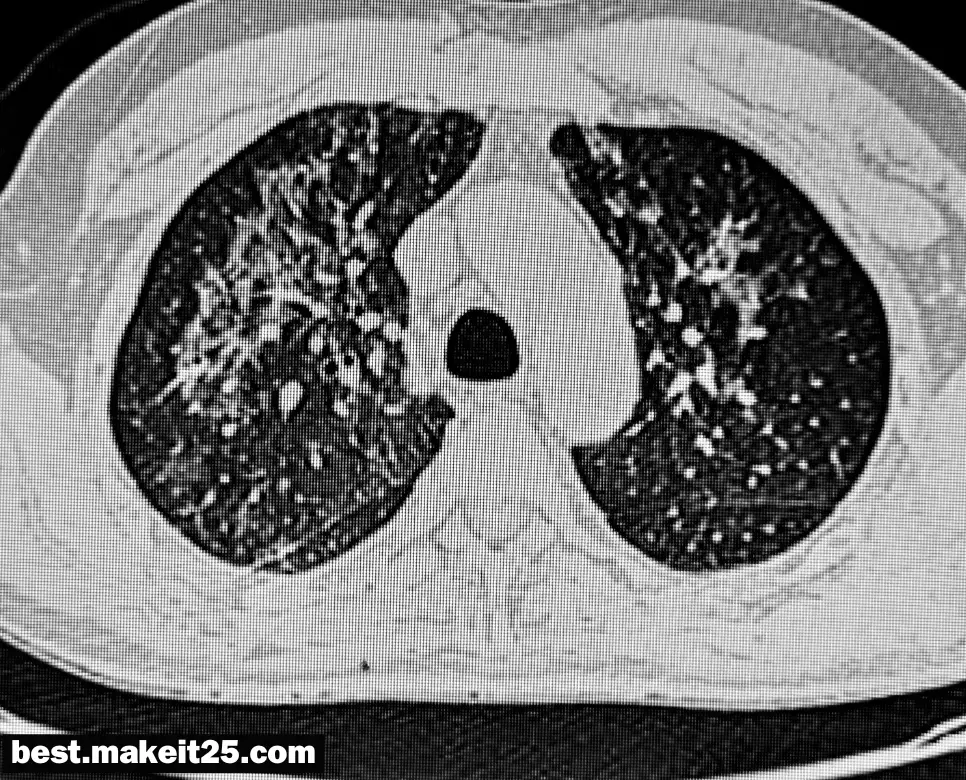

PCP는 ‘Pneumocystis Pneumonia’의 약어로, 한국어로는 ‘폐포자충 폐렴’을 의미합니다. 이는 주로 면역체계가 약화된 환자들에게 발생하는 기회감염성 폐렴으로, 폐포자충이라는 특정한 유형의 기생충에 의해 발생합니다. PCP는 에이즈 환자, 항암 화학요법을 받는 암 환자, 장기 이식 후 면역 억제제를 복용하는 환자 등 면역력이 저하된 환자들에게서 주로 발생하며, 면역력이 정상인 사람에서는 거의 발생하지 않습니다.

PCP의 원인균은 ‘Pneumocystis jirovecii’로, 이는 공기 중에 널리 분포하는 기회감염성 진균입니다. 이 균은 면역력이 저하된 사람의 폐포에서 증식하여 폐렴을 일으키게 됩니다.

- 영상 검사: 흉부 X-레이나 CT를 통해 폐의 상태를 확인합니다.

- 검사실 검사: 기관지폐포세척액(BAL)이나 객담에서 PCP 원인균을 확인합니다.